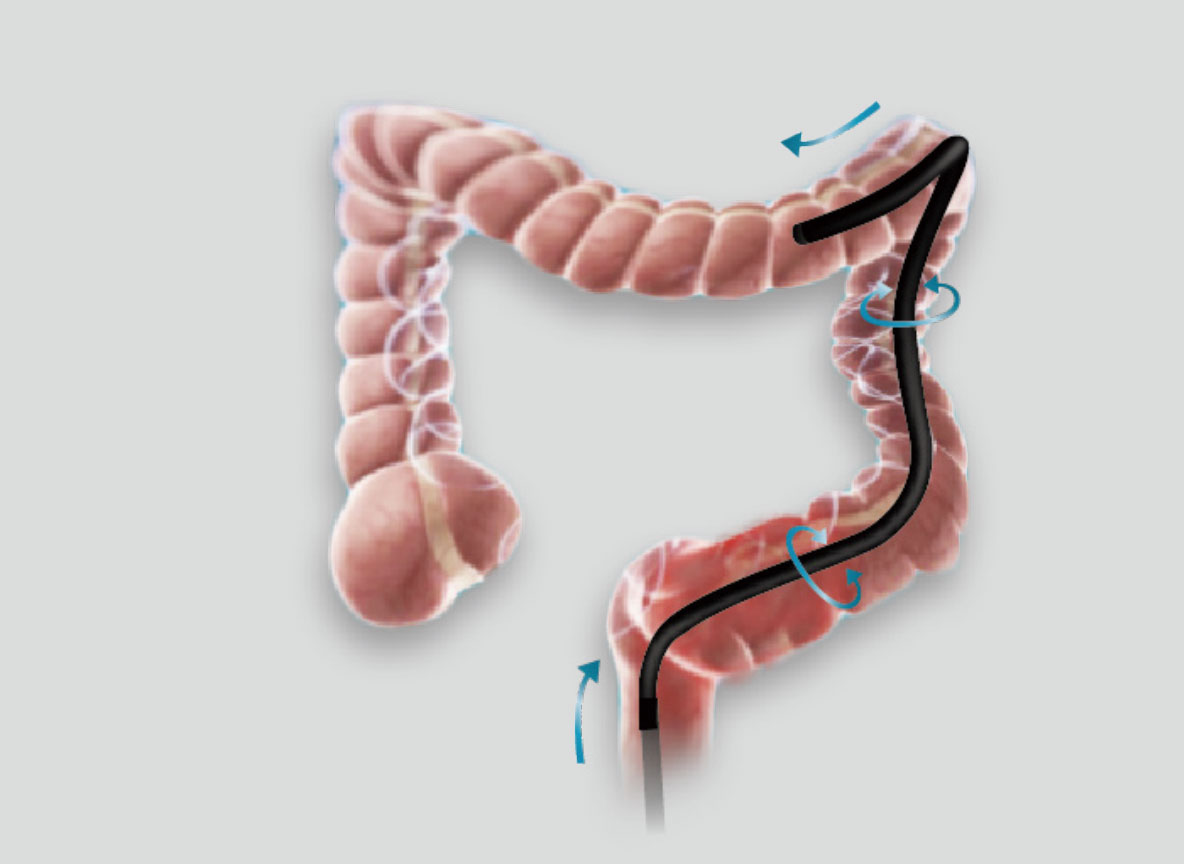

弯曲半径小,角度大,方便观察食管下段贲门、胃底部等难以观察到的部位,减少盲区。

带来镜体插入及诊疗新体验。